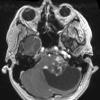

NEOPLASMS (GLIAL)

Astrocytoma, pilocytic - Microscopic (12)